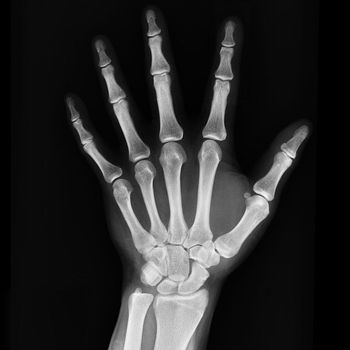

John Botson, MD, defines gout and how it can be treated.